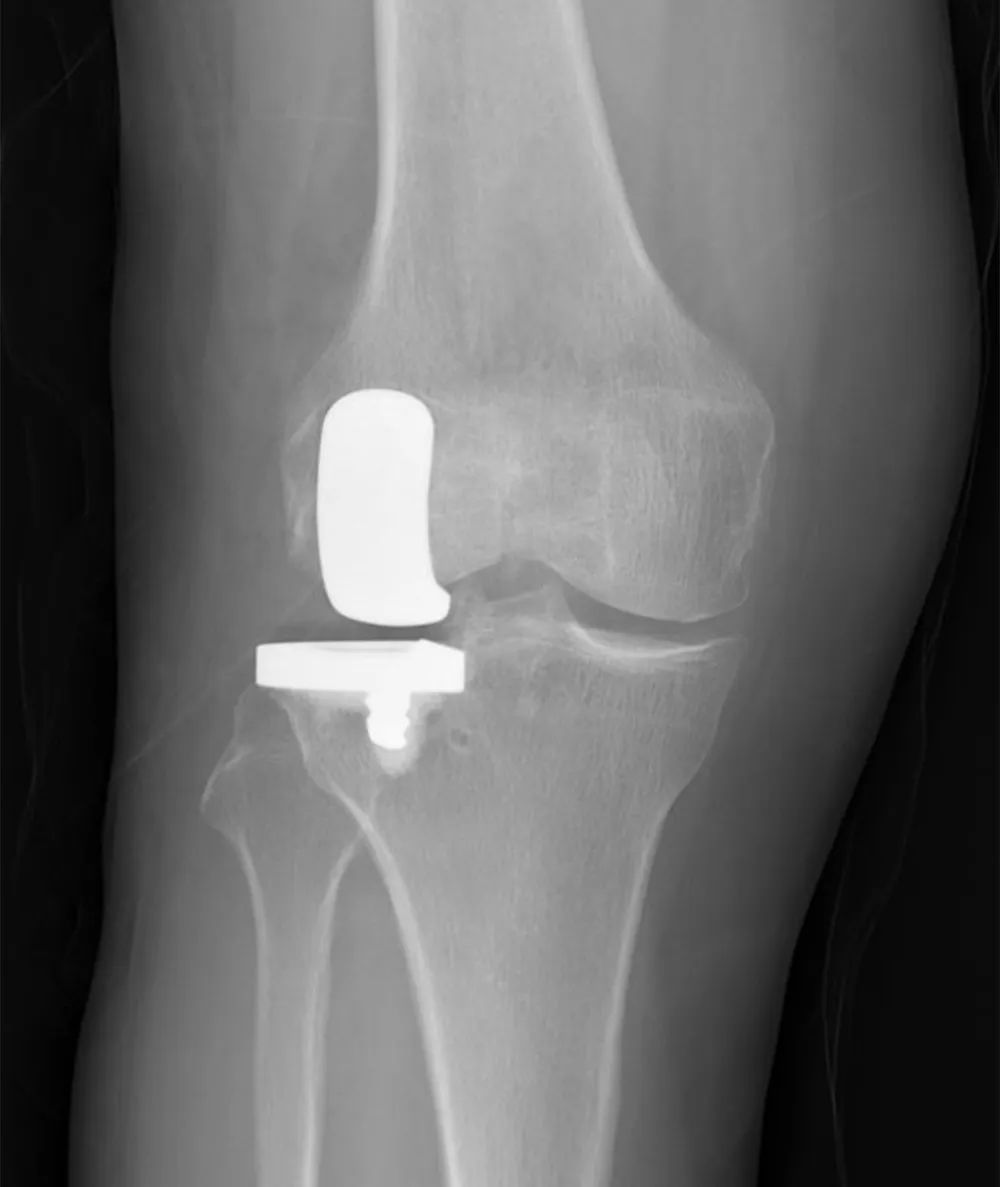

手术进行了1个小时,很顺利。术后X光片显示,假体大小选择合适,假体位置精准植入,术后功能恢复良好。术后第一天,张女士的右膝关节屈曲达到120°以上,不用扶拐就能行走。

术后复查X光片